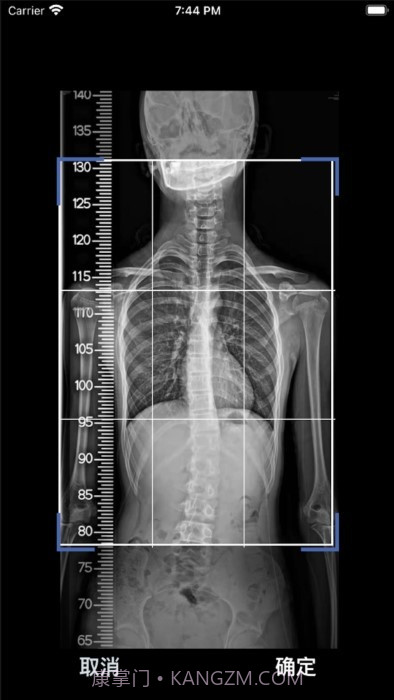

这款cobb角测量分析平台简直是医生和脊柱侧弯患者的福音!🌟 通过智能测量功能,能够迅速获取cobb角,准确率高得让人放心呢。对于有脊柱健康需求的小伙伴们来说,了解自己的状况特别重要,不仅能省时省力,更能随时存储和导出数据,后续分析也是轻松搞定!总之,这款应用为提高医疗效率、帮助患者掌握健康状况提供了强有力的支持,真心推荐给大家!

AI算法真牛,自动识别速度飞快,不用再手动调整。

应用使用AI自动识别椎骨,确保精确度高达95%,让你用得放心。